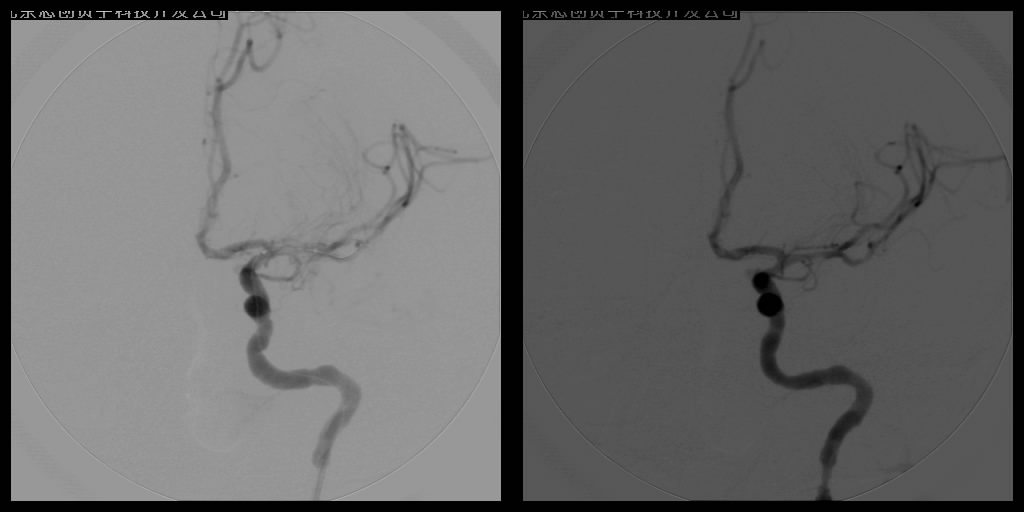

1.血管内动脉溶栓术

血管内溶栓有区域性动脉内溶栓、早期超选择动脉内接触性溶栓和静脉窦接触性溶栓。区域性动脉内溶栓适用于颅内大血管栓塞和血栓形成,如颈内动脉和椎-基底动脉内。早期超选择动脉内接触性溶栓适用于颈内动脉以上的各分支大小血管的闭塞和椎-基底动脉系统闭塞。

血管内溶栓及机械取栓

2.动脉血管成形术

针对颈动脉和椎基底动脉狭窄等缺血性脑血管病的防治,血管球囊扩张成形术和血管内支架植入成形术已经成为治疗颈动脉狭窄及椎基底动脉狭窄十分重要的手段,所用支架可分为球囊扩张式支架和自膨式支架。